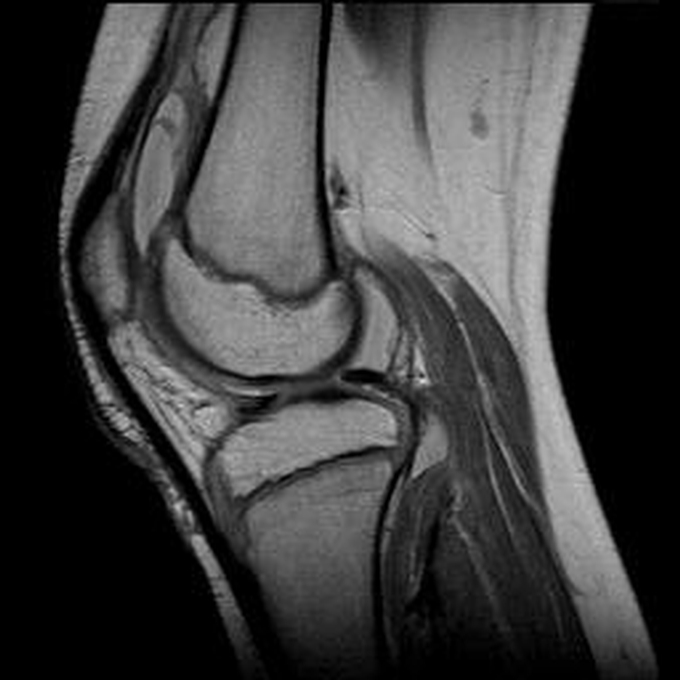

Haemophiliearthropathie bei Haemophilie A.

Arthropathia ARC123 Haemophiliearthropathie bei Haemophilie A.

MRT (high)